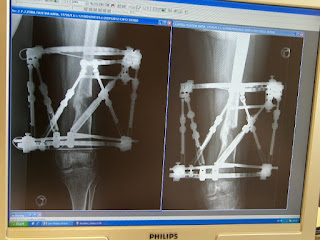

Verlaufsprotokoll meiner Beinkorrektur im linken Oberschenkel in mehreren Achsen: Geradestellung des X-Knies um 6° plus Beinverlängerung am Oberschenkel um 3,5 cm. Wie geht das: Mit dem Taylor Spatial Frame = externer Ringfixateur, der mehrdimensionale Korrekturen graduell ermöglicht. OP: 30.Juni 2009, Abnahme: 15. März 2010 = 37 Wochen. Drehtage netto: 44. Fragen und Rückmeldungen gerne an beinkorrektur@gmx-topmail.de

An der Außenseite will das Knochenwachstum nicht so richtig "anspringen". Der Knochen hat sich zwar innen schon schön verdichtet, aber es reicht nicht, um den Apparat zu entfernen, weil dann die Bruchgefahr zu groß wäre. Im Moment trägt einen Großteil des Gewichts ja der Apparat und der Knochen ist in diesem Bereich nur zur Hälfte (an der Innenseite) vorhanden.

Hier eine Vorderansicht mit Vergleich vom 1.12. (li) und 28.12. (re):

Die Knochenverdichtung an der Außenseite sieht man aber an der Seitenansicht sehr schön (li: 1.12., re: 28.12.):